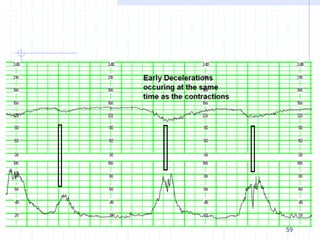

Early Decelerations

A gradual decrease and return to baseline of the

FHR associated with a uterine contraction

The nadir of the FHR and the peak of the

contraction occur at the same time

Caused by fetal head compression during uterine

contraction, resulting in vagal stimulation and

slowing of the heart rate

not associated with fetal distress and thus are

reassuring

59